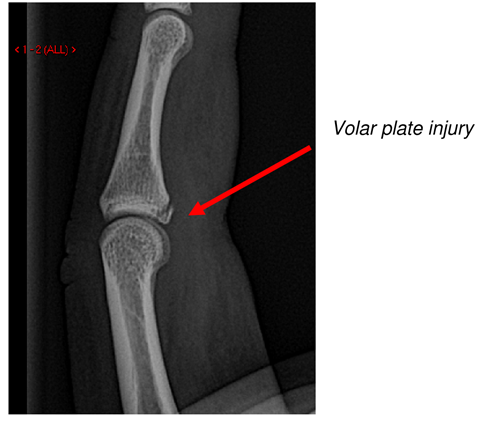

- Volar Slabs are used for un-displaced fractures which are potentially unstable. They are applied with the hand in the “position of function” with finger MCP joints flexed and IP joints extended which avoids stiffness. A thumb extension can be added for thumb fractures.